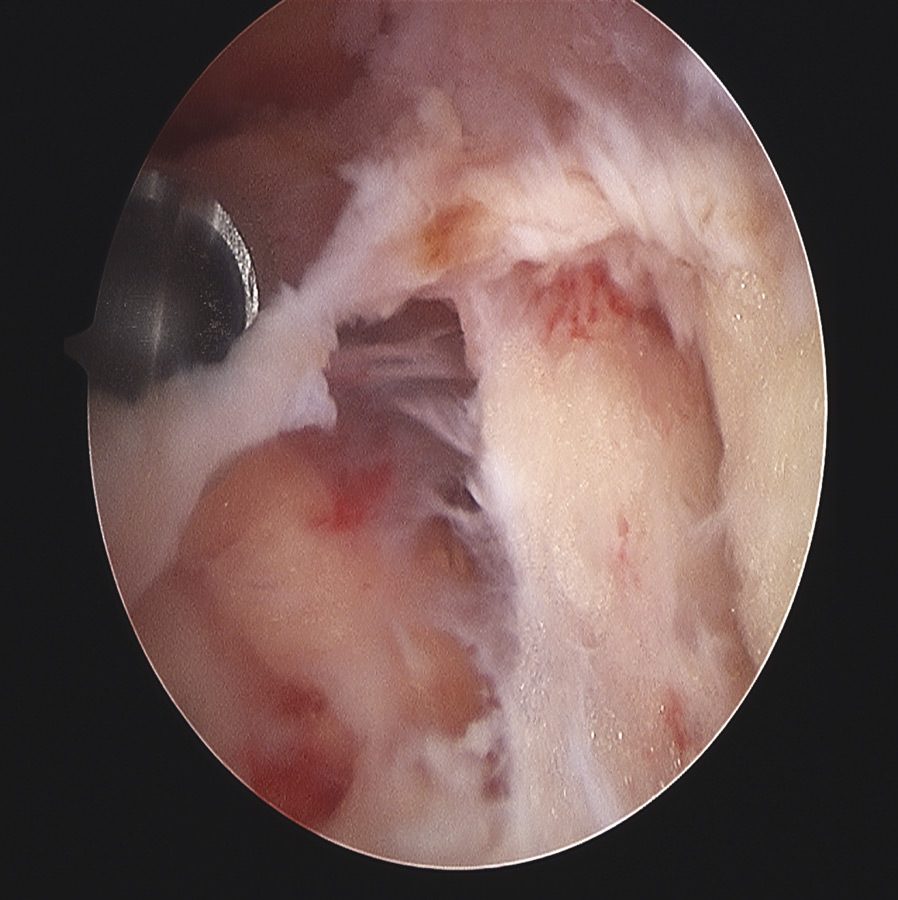

Siguiendo por los recesos lateral y medial (Figura 5) se llega a la zona suprapatelar, cuya fibrosis es la primera causa de limitación de la flexión (Figura 6). En este espacio hay que ser muy meticuloso para resecar con motor (Figura 7) y radiofrecuencia las adherencias, los nódulos, cíclopes (Figura 8), la fascia profunda del cuádriceps, con esqueletización de la cara anterior de fémur si es necesario, y liberar el alerón externo e interno, en función de la rótula: si está lateralizada (liberación solo lateral) o bien centrada (liberación lateral y medial), para facilitar el recorrido rotuliano. La limpieza de este espacio es fundamental para recuperar el máximo grado de flexión.

Figura 5. Fibrosis en el receso medial en la rodilla rígida.